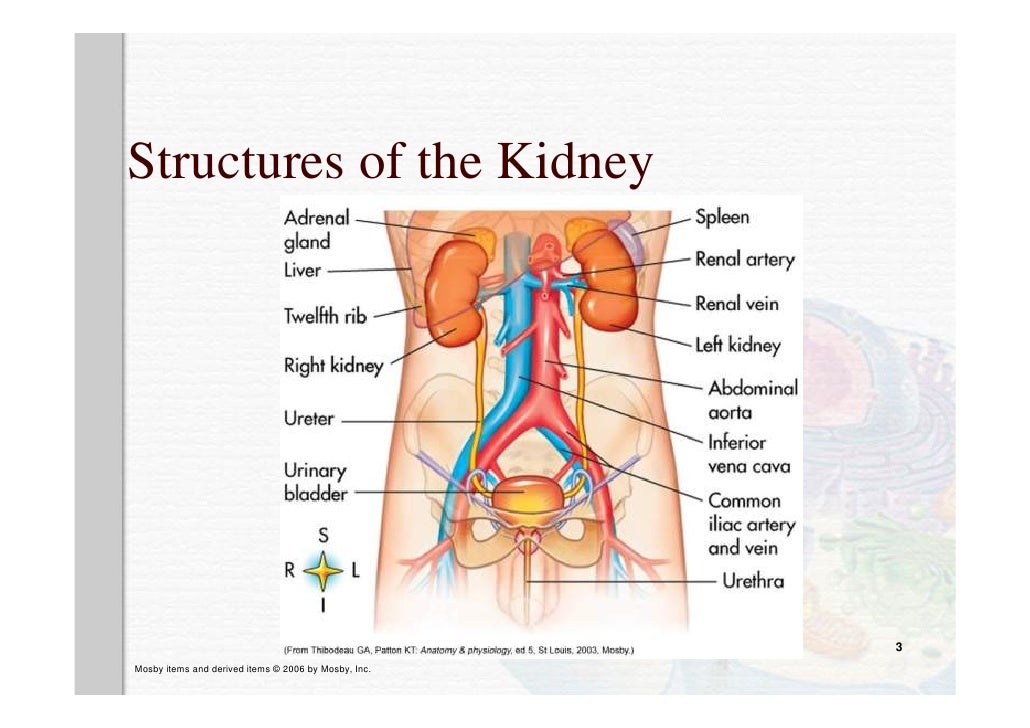

The kidneys are 11 centimeters long paired reddish brown organs situated on the posterior wall of the abdominal cavity one on each side of the vertebral column and capped by the adrenal gland. H ions are produced as a natural byproduct of the metabolism of dietary proteins and accumulate in the blood over time. Connective tissue anchors the kidneys to surrounding structures and helps maintain their normal position.

Upper portions of the kidneys are somewhat protected by the eleventh and twelfth ribs figure 1. Anatomy of the kidneys. Each kidney weighs about 125175 g in males and 115155 g in females.

Due to the presence of the liver the right kidney is slightly lower than the left kidney. They are about 1114 cm in length 6 cm wide and 4 cm thick and are directly covered by a fibrous capsule composed of dense. Anatomy of the urinary system.

The kidneys monitor and regulate the levels of hydrogen ions h and bicarbonate ions in the blood to control blood ph. Glomerular filtration glomerular filtration is the renal process whereby fluid in the blood is filtered across the capillaries of the glomerulus. The right kidney is lower than the left due to displacement by the liver.

Location of the kidneys there are two kidneys which lie retroperioneally in the lumbar area. The angiotensinconverting enzyme converts angiotensin i to angiotensin ii which stimulates the adrenal cortex to secrete aldosterone a hormone that is involved in increasing blood pressure. The basic anatomy and physiology of the kidney how kidney function changes through life the anatomy of the kidney the kidneys are comple x and beautiful organs.